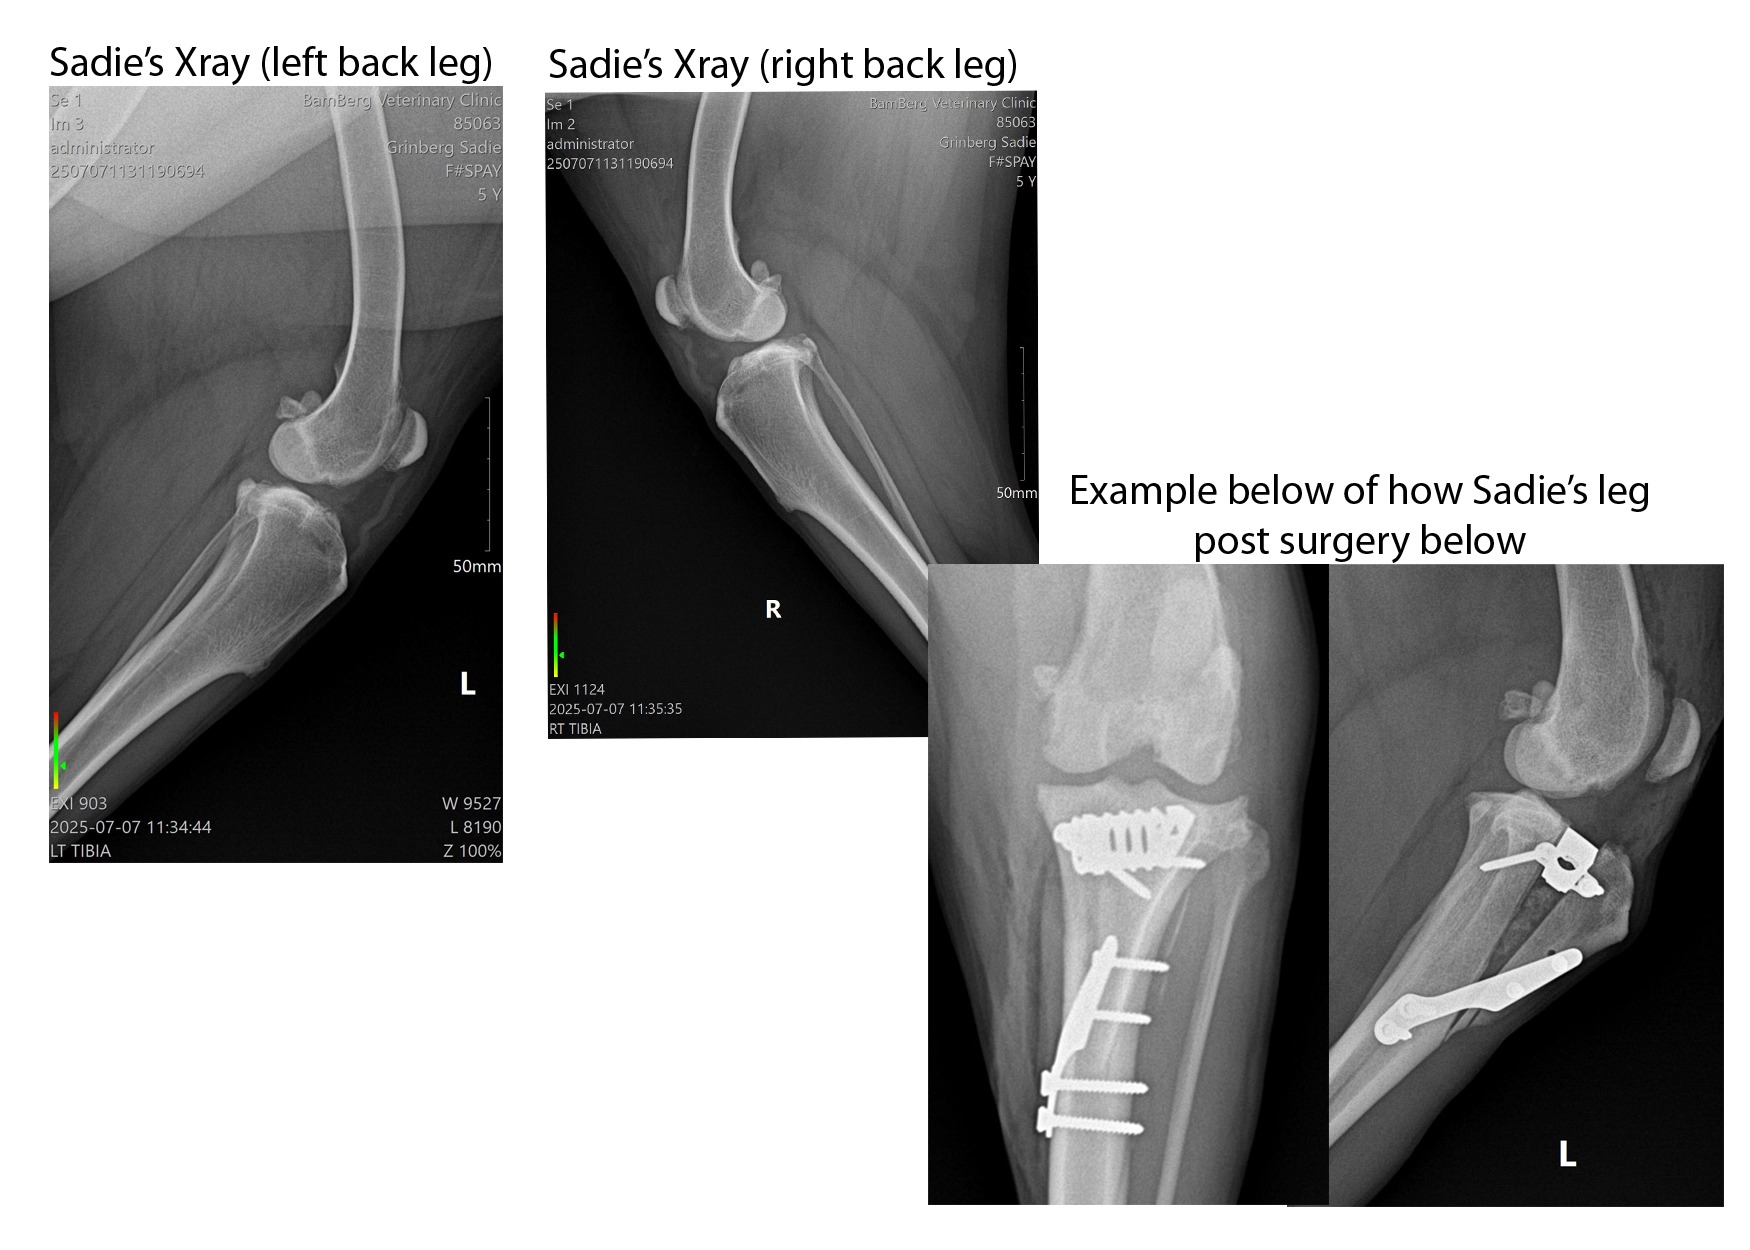

Surgeon consult: We checked with several clinics; that priced the required surgery at 8-10k for TTA (Tibial Tuberosity Advancement) After researching, we found a clinic willing to do this surgery for $1900-$2100. A wonderful man who adores country vet care living and helping those who love their fur babies. He is no-nonsense and straight to the point, explaining he would not do the surgery if he did not feel it would help her walk again. He has just completed this same surgery on his fur baby. Recovery time is 12 weeks in her kennel, which she loves, thank goodness, and a leash to potty outside. She will eventually need the right leg done, but the left leg seems to be causing her more pain than the other at this point. He also confirmed our suspicions that his opinion of Sadie’s diagnosis is of a previous injury in her early months of life. We will never know whether it resulted from the owner kicking or hitting her. What we do know is her legs appear with previous breaks fused back together, which has caused arthritis to set in. This is causing the decrease in mobility and use of the leg now.